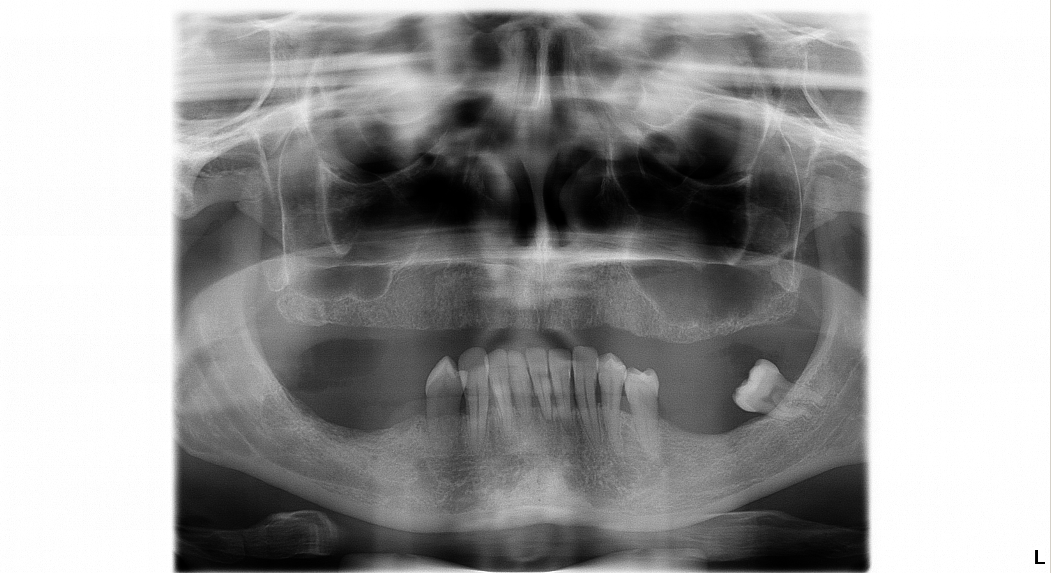

Pacientka Eva podstúpila implantáciu hornej a aj spodnej čeľuste v celkovej narkóze. Vo vrchnej čeľusti pacientka nosila snímateľnú protézu, ktorá vzhľadom na jej vek nebola dobrým riešením. Preto sa rozhodla pre radikálnu zmenu. A ako napísala v dotazníku po ošetrení bola veľmi spokojná s finálnym výsledkom.

Vedeli by ste nám poslať RTG snímku, alebo fotografiu Vašich zubov? Záleží od toho koľko zuby sme museli trhať, koľko implantátov by bolo potrebných a pod.

Poprípade by nám pomohlo, ak by ste nám poslali aspoň Vašu OPG rontgenovú snímku emailom, aby sme mali predstavu o stave Vášho chrupu a vedeli Vám povedať bližšie informácie o cene.